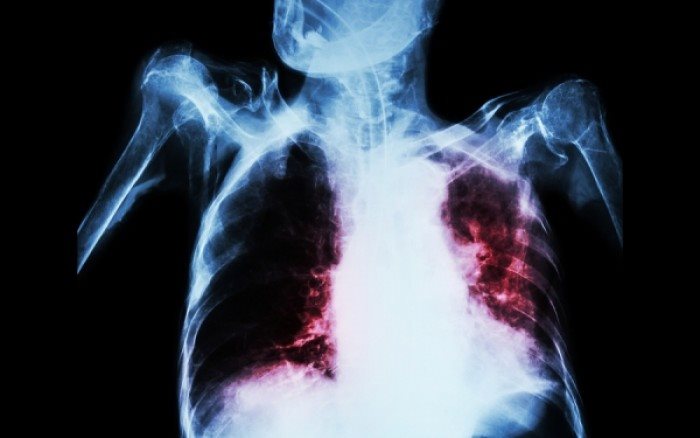

Με «καινούριο» πρόσωπο εμφανίζεται πλέον η φυματίωση

Σε σοβαρό πρόβλημα δημόσιας υγείας αναδεικνύεται τα τελευταία χρόνια η φυματίωση, η οποία εκδηλώνεται πλέον με καινούργιο πρόσωπο, και συγκεκριμένα με μορφές ανθεκτικές στα αντιφυματικά φάρμακα. Ωστόσο, το φαινόμενο δεν είναι αμιγώς ελληνικό.

Δεν υπάρχει πλέον στο κόσμο χώρα που να μη δηλώνει έστω και μια περίπτωση εκτεταμένα ανθεκτικής φυματίωσης, δηλαδή ανθεκτικής σε όλα τα διαθέσιμα φάρμακα για τη νόσο.

Δυστυχώς όμως, στην Ελλάδα δεν υπάρχει επάρκεια σε δομές νοσηλείας και αντιμετώπισης αυτών των μορφών φυματίωσης. Η χώρα μας διαθέτει μια μόνο μονάδα πολυανθεκτικής φυματίωσης, με μόλις επτά (7) κλίνες σε θαλάμους αρνητικής πίεσης, η οποία καλείται να διαχειρισθεί τα σχετικά περιστατικά όλης της χώρας.

Παράλληλα, τα τελευταία χρόνια έχει αυξηθεί στη χώρα μας το ποσοστό συμμετοχής των αλλοδαπών στη διαμόρφωση της συνολικής συχνότητας της φυματίωσης, καθώς και αύξηση των κρουσμάτων της νόσου σε ευάλωτους πληθυσμούς, όπως οι κρατούμενοι, οι ναρκομανείς και οι φορείς του HIV.